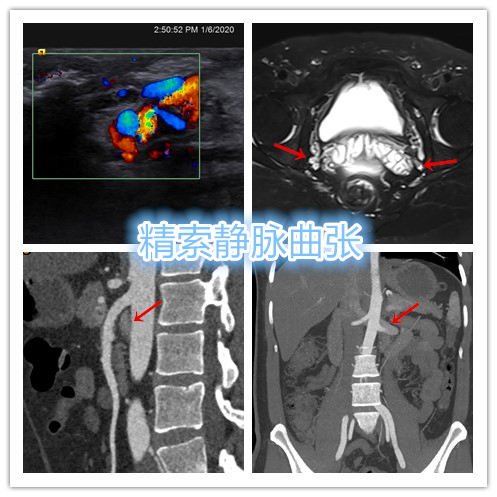

精索静脉曲张

精索静脉曲张是指静脉瓣膜功能不全或者血流受阻,血液返流引起精索静脉内血流瘀滞,导致蔓状静脉丛异常的迂曲扩张。男性总体人群中精索静脉曲张的发病率为10%~15%,多为青壮年,80%~98%发生在左侧,发生于右侧者约为10%,双侧发病者也约为10%。

彩超检查是诊断精索静脉曲张的首选方法,具有十分重要诊断价值。彩超可以同时显示二维图像及其血流情况,对精索静脉曲张诊断准确率约为98%,总敏感度可达100%。

- 彩超检查显示双侧精索静脉曲张,彩超及CTA显示左肾静脉回流顺畅,未见狭窄返流,排除“胡桃夹综合征”。